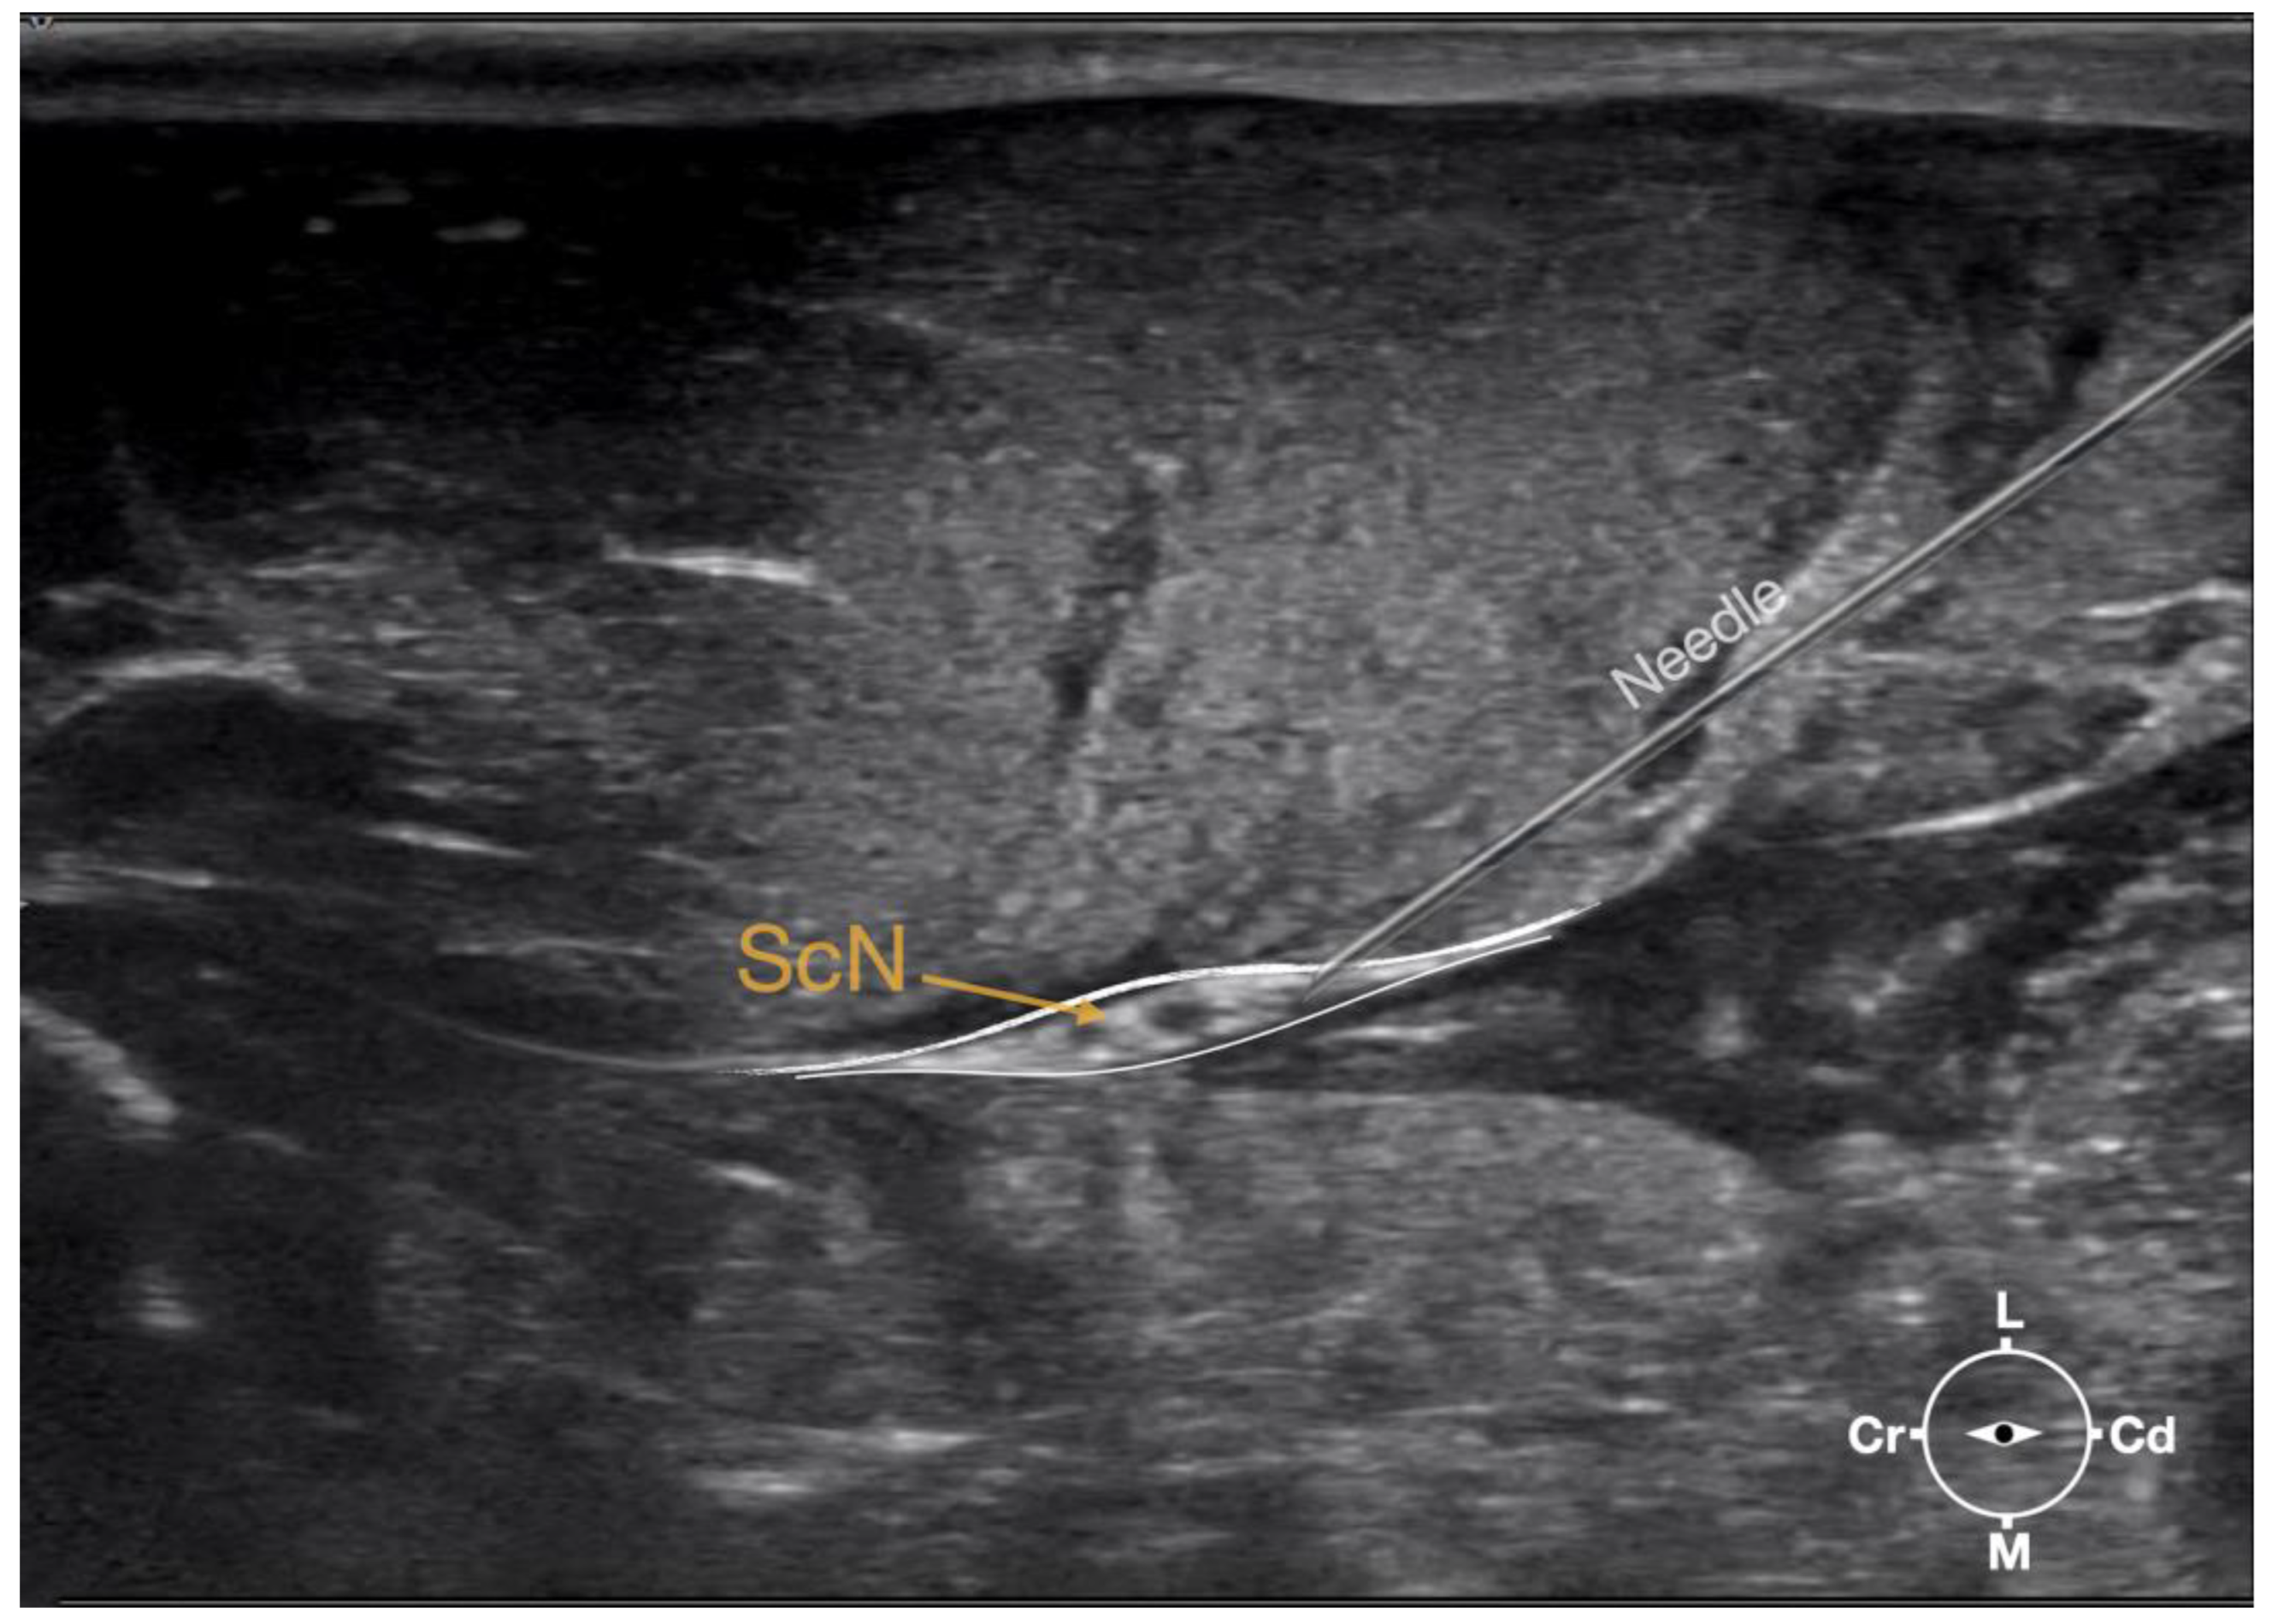

2.3.1. Sciatic Nerve Injection

First, the cadaver was positioned in lateral recumbency. Then, the area of interest was clipped. A 18-4 MHz linear transducer (L 18-4, Konica Minolta, Ramsey, NJ, USA) attached to an ultrasound machine (HS1, Konica Minolta, USA) was used and ultrasound gel (Softa-Man, ViscoRub, B. Braun, Maria Enzersdorf, Austria) was applied to facilitate acoustic coupling. The transducer was placed in transverse position, at the level of the proximal third of the femur but caudal to the bone with a window of interest set at a depth of 3 cm to optimize the image. Then, the transducer was slightly rotated clock or anticlockwise to obtain a transverse image of the sciatic nerve (Figure 1). A 50 mm 22-gauge insulated needle (Sonoplex Stim Cannula, Pajunk Medical Produkte GmbH, Geisingen, Germany) prefilled with a solution of L-NMB was inserted using an in-plane approach. The needle was inserted at the caudal end of the transducer and advanced in-plane under sonographic guidance through the biceps femoris muscle in a cranio-medial direction towards the sciatic nerve (Figure 2). The needle was advanced until its tip punctured the muscular fascia enveloping the sciatic nerve (Figure 3). A test volume of 0.05 mL of L-NMB was injected to confirm adequate distribution inside the interfascial space that contained the sciatic nerve. The remaining volume of 0.15 mL/kg was then injected perineurally around the sciatic nerve.

Figure 1. Corresponding transverse ultrasound image to Figure 2. The ultrasound image shows the sciatic nerve and related structures. The depth was set at 3 cm and the focus was placed at the level of the sciatic nerve. The white lines indicate the muscular fascia enveloping the sciatic nerve. Cr, cranial, Cd, caudal; L, lateral; M, medial.

Figure 3. Ultrasonographic image demonstrating the approach of the needle towards the sciatic nerve. Depth at 3 cm and focus on the level of the nerve. ScN, sciatic nerve; Cr, cranial; Cd, caudal; L, lateral; M, medial.